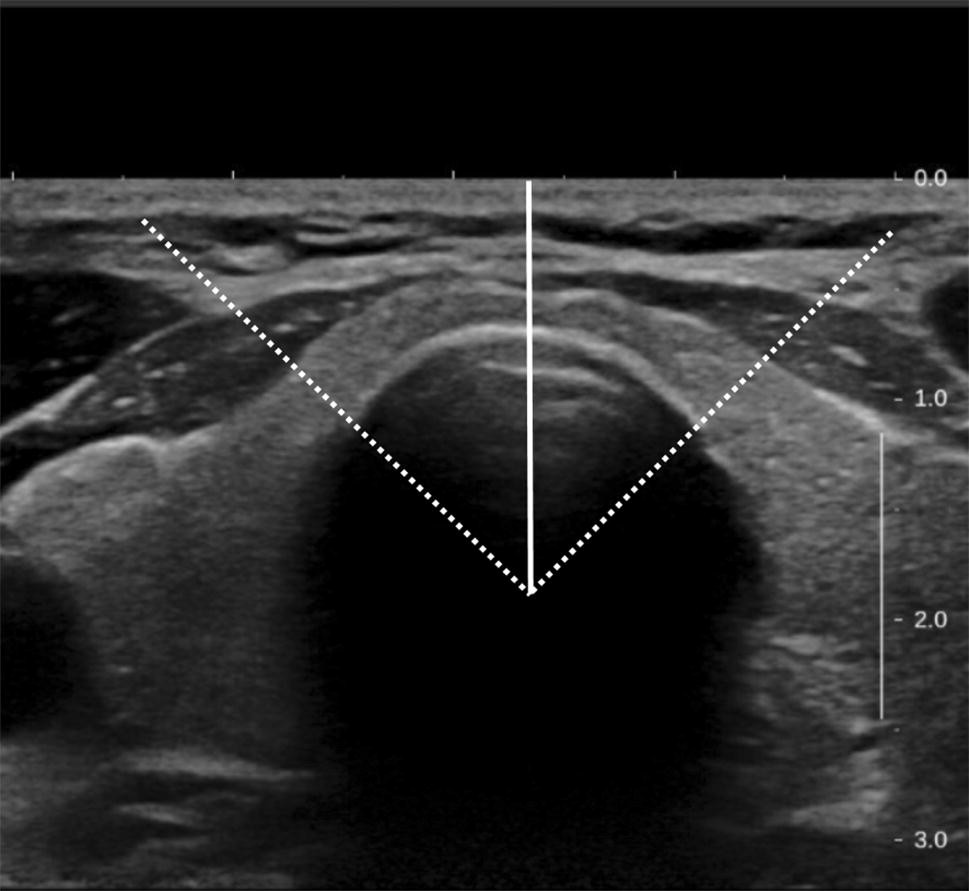

Isthmus Of Thyroid

Thyroid: What It Is, Function & Problems Thyroid - Wikipedia Definition of thyroid - NCI Dictionary of Cancer Terms - NCI The Thyroid Gland - Location - Blood Supply - TeachMeAnatomy Thyroid Anatomy & Physiology - Miami Endocrine Surgery Isthmus Of Thyroid